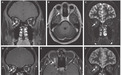

入院 MRI 如图 A-C,按照「非典型视神经炎」治疗后 MRI 如图 D-F,症状无改善。

图A、B是增强,C是冠位的T2图D、E是增强,F是冠位T2。E在T1WI 增强基础上做了压脂,所以看起来比图 B在眼眶里面的病变现实更清楚。

两次强化都很均匀,肿胀很明显,一般视神经炎没有这么肿胀,并且这么均匀的强化的

答案其实就在 MRI 结果上。一开始的 MRI 就能看出有肿块样视神经病变,经过甲泼尼龙治疗后,病变尺寸没什么变化,说明很可能是肿瘤,这个部位最常见的肿瘤是视神经胶质瘤或视神经鞘脑膜瘤。

视神经胶质瘤发病年龄通常在 20 岁以下,本例患者不那么符合;而视神经鞘脑膜瘤一般具有特征性「双轨征」,本例患者也不太符合。

影像学上无法立刻诊断,取眼眶标本活检,肿瘤细胞孕激素受体弥漫性核染色,提示低级别脑膜瘤;病理提示脑膜上皮型脑膜瘤,最终诊断为「上皮型视神经鞘脑膜瘤」。